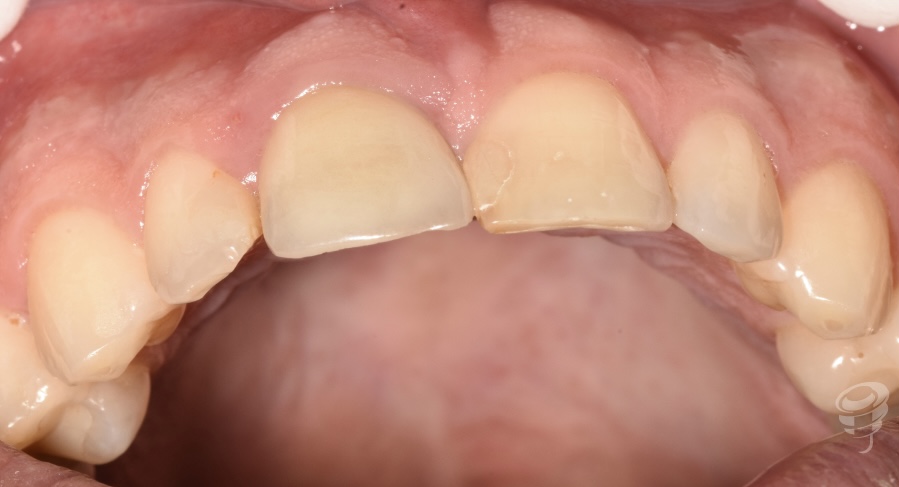

Caso Clínico | Rehabilitación Estética Integral con implante inmediato, injerto óseo y de tejido conectivo y carillas de cerámica en incisivo central superior fracturado

- Caso clínico: Paciente masculino de 45 años con fractura irreparable del incisivo central superior derecho (11) previamente tratado con una endodoncia y unión colado, fracturado por trauma oclusal. Se realizó extracción atraumática, colocación de implante inmediato, injerto óseo xenogénico mezclado con hueso antólogo del fresado, e injerto de tejido conectivo subepitelial para optimizar el perfil de emergencia. A los 4 meses se colocó corona implanto-soportada de zirconio y carillas de disilicato de litio en dientes 12 y 21.

La pérdida de un incisivo central superior por trauma representa un desafío estético y funcional de alta exigencia. Los implantes inmediatos, combinados con procedimientos de regeneración ósea y de tejidos blandos, permiten preservar la arquitectura alveolar y gingival, minimizando el tiempo de tratamiento y mejorando la predictibilidad estética (1).

Figura 2